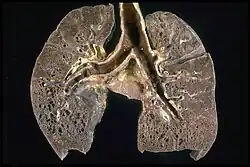

Pathologisches Präparat einer Lungensarkoidose im Endstadium. Deutlich zu erkennen ist eine Vielzahl von kleinen Zysten mit verdickter Wand (‚Honigwabenlunge‘, engl. honeycombing).